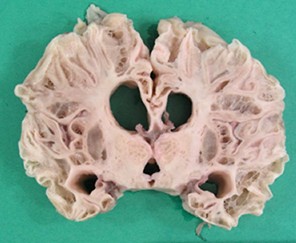

- Multicystic encephalopathy

- diffuse cortical and subcortical white matter necrosis

- results in lace-like cavities

- late occurring lesion during partuition or first postnatal month of term pregnancy

- can be due to infectious encephalopathy, e.g., CMV, toxoplasmosis, listeria

- can be due to twin-twin transfusion